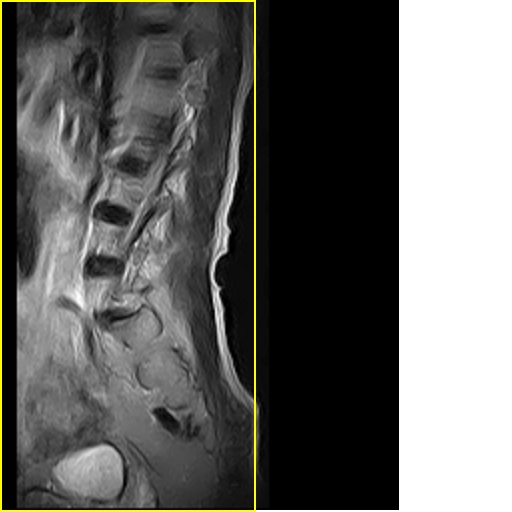

标题: MRI0859:[原创]腰椎,男,78岁,右下肢跛行两月 [打印本页]

标题: MRI0859:[原创]腰椎,男,78岁,右下肢跛行两月

男,78岁,右下肢跛行两月.

右侧黄韧带肥厚或钙化,压迫马尾神经所致。必要时行ct扫描。

腰间盘膨出、黄韧带肥厚、可疑先天性腰椎管狭窄。

退行性病变:增生、椎间盘变性、膨出[l4-5、l5-s1 椎间盘膨出]